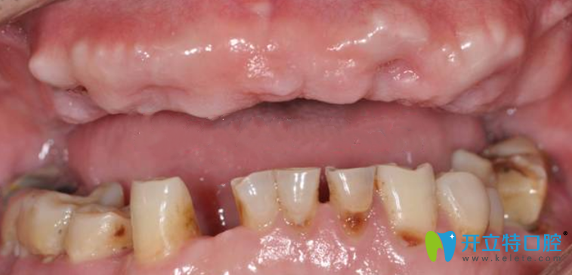

手術(shù)前:

在南京金臺口腔田忠奎院長診斷,張叔的牙齒屬于半口牙缺失,牙齒根部有的已經(jīng)壞掉。目前有兩種解決辦法種植牙和烤瓷牙,田院長科普了種植牙和烤瓷牙的區(qū)別后,張叔毫不猶豫的選擇了即刻種植牙齒,安全有效,節(jié)省時(shí)間,立拔立種,當(dāng)天種當(dāng)天用。